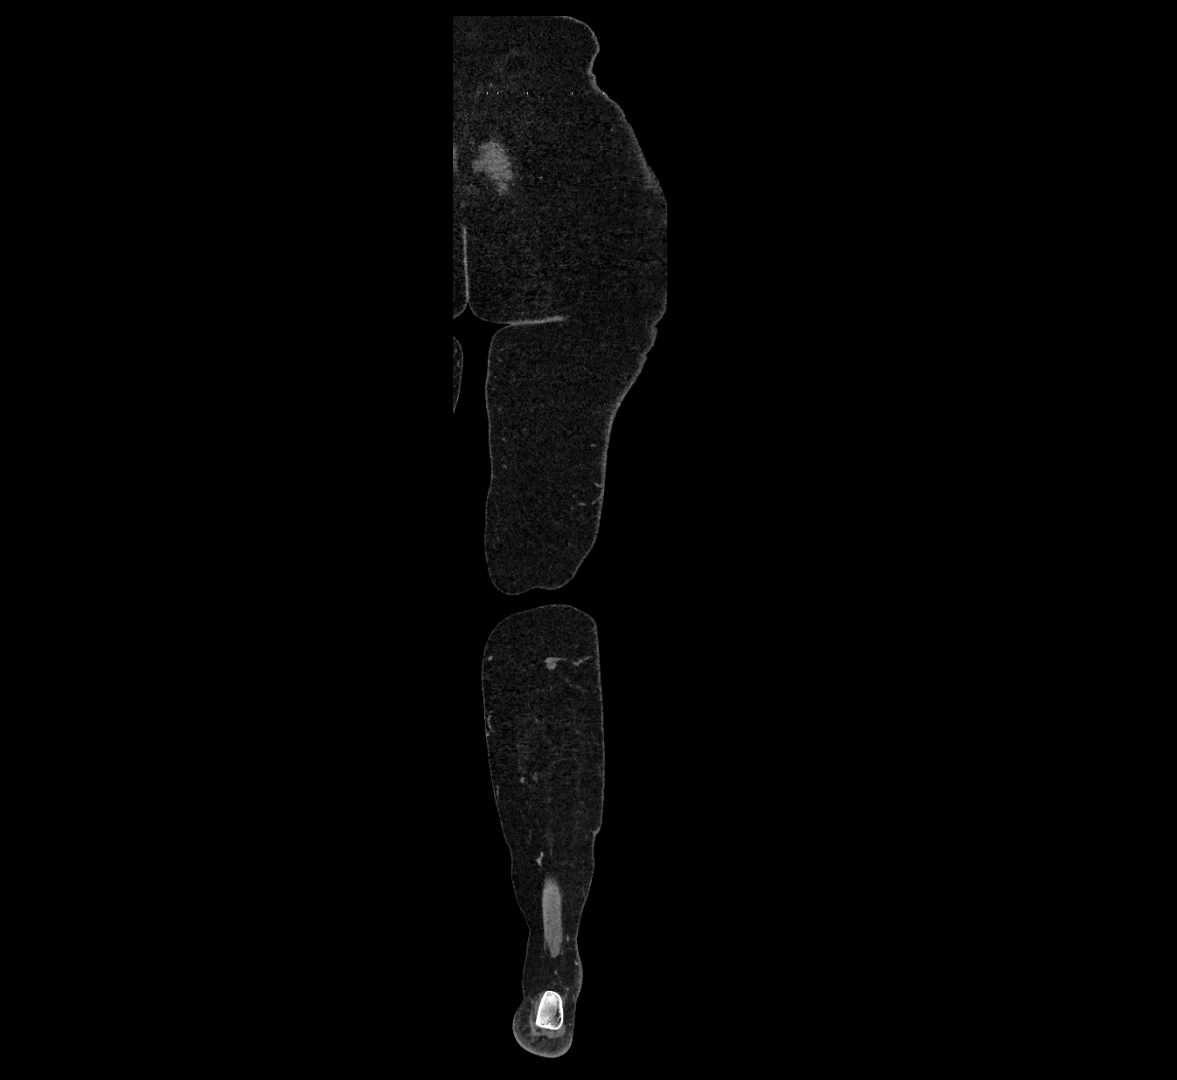

Contrast-enhanced CT (CTA):

• Gold standard for abdominal aortic imaging

• Provides excellent detail of lumen, wall, aneurysm, thrombus, and branch vessels

• Multiplanar and 3D reconstructions help in aneurysm measurement, stent graft planning, and dissection evaluation